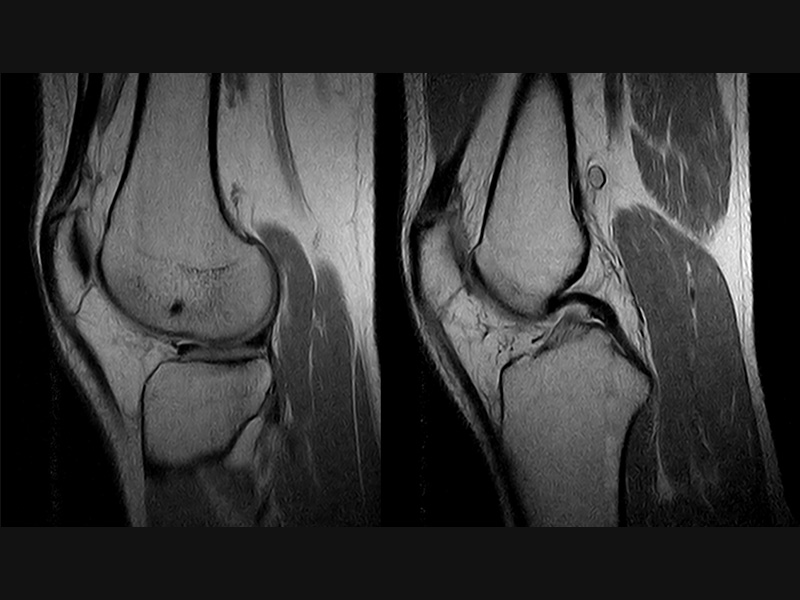

Klinické snímky